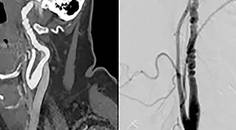

Pseudotumor Cerebri Syndrome Related to a Dural Arteriovenous Fistula After Vascular Trauma

Andrew Anastos, BS; Misha Pless, MDAndrew Anastos, BS; Misha Pless, MD - Headache & Pain